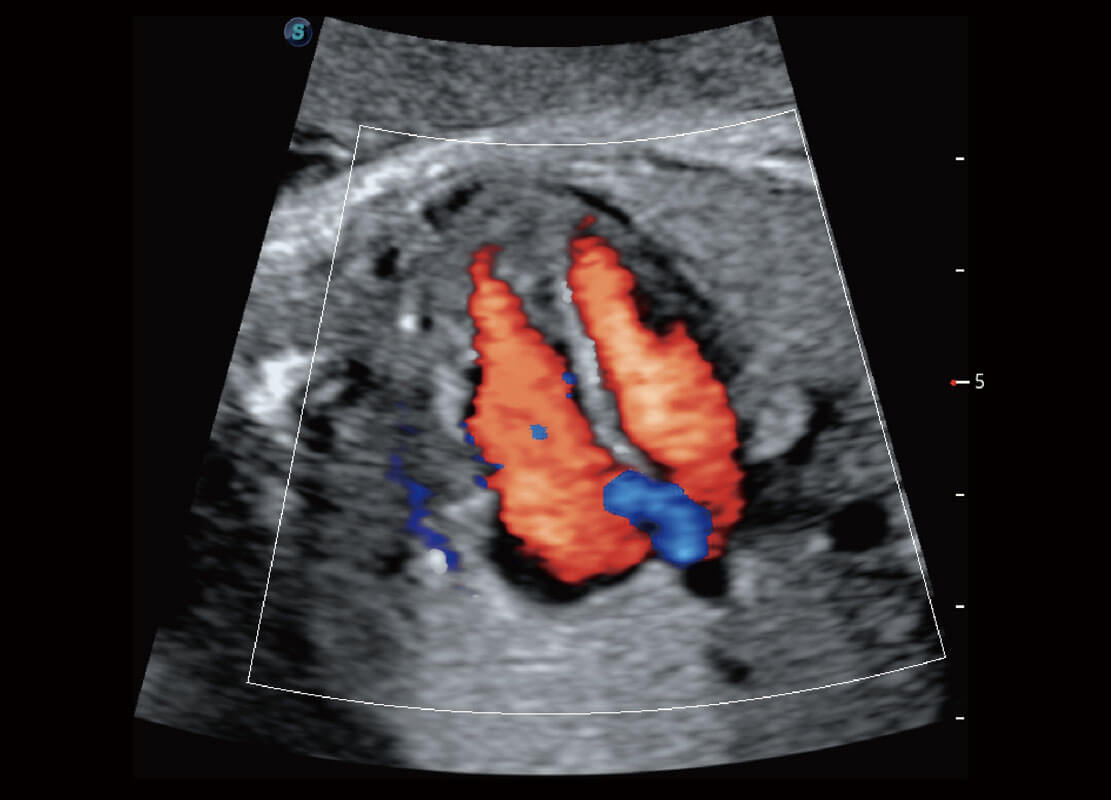

四腔心血流

P60搭载一系列胎儿心脏成像技术,实现精细的胎儿心脏评估。